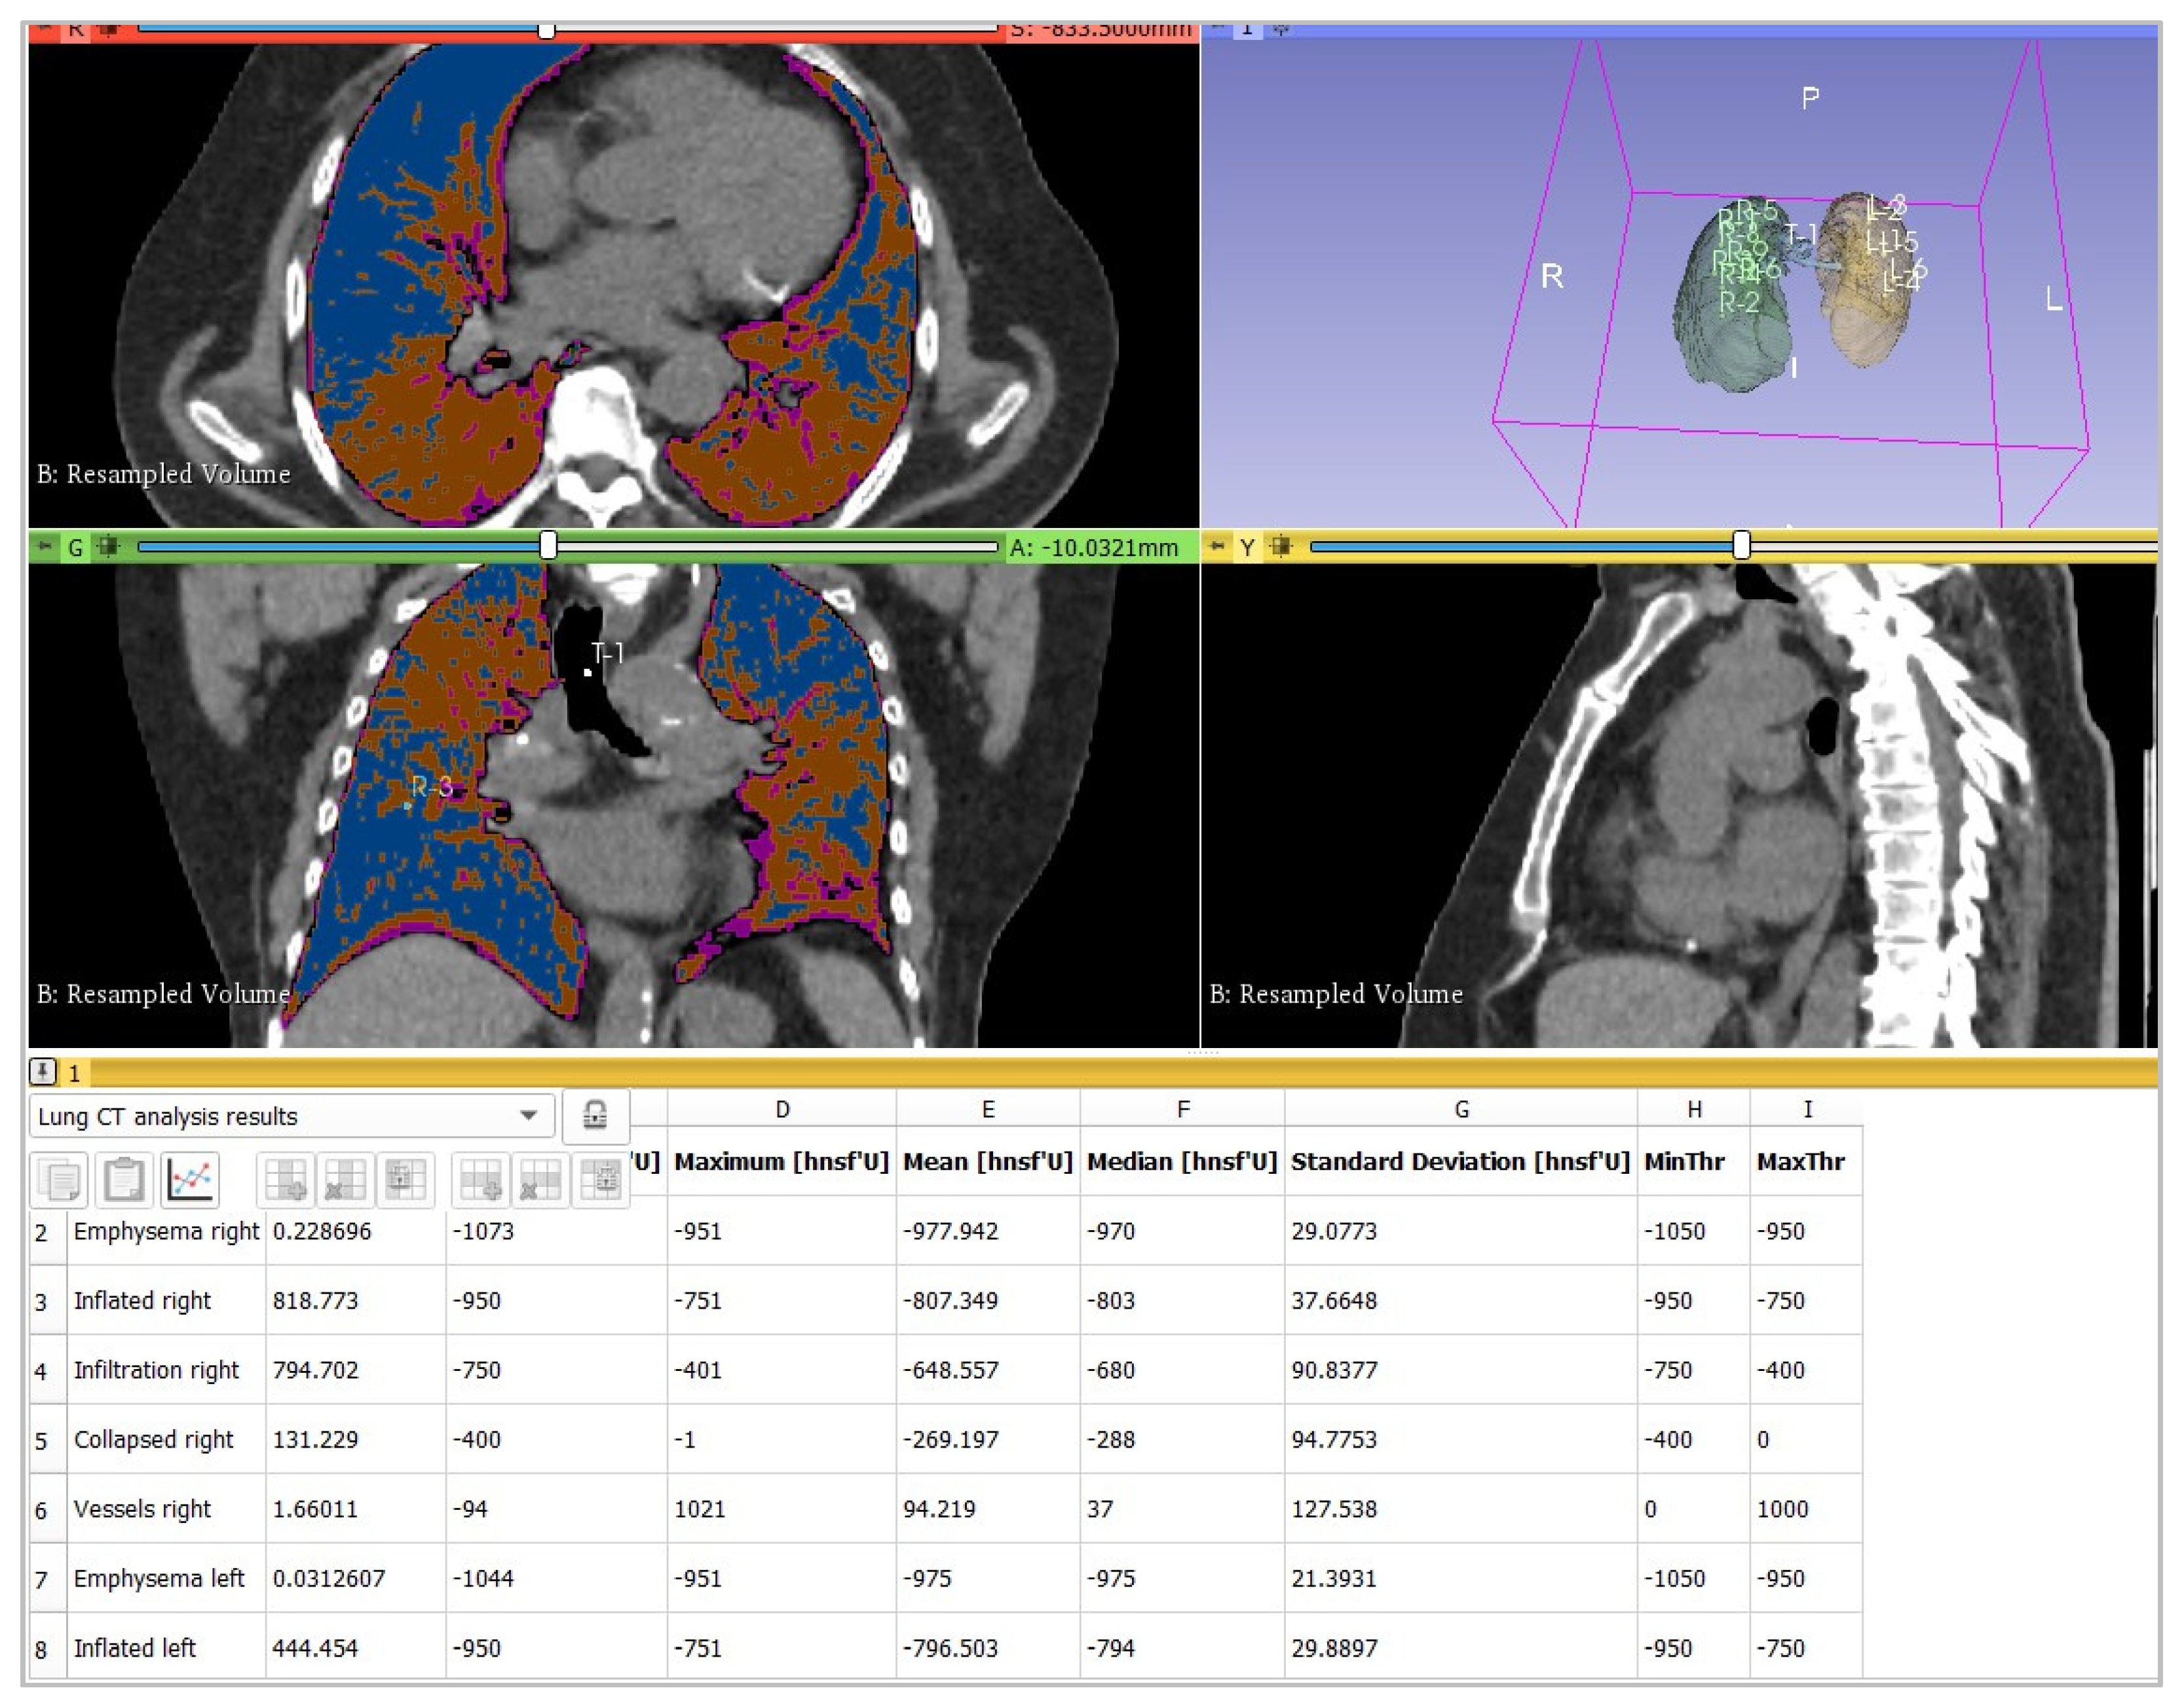

2.3. Image Analysis

- -